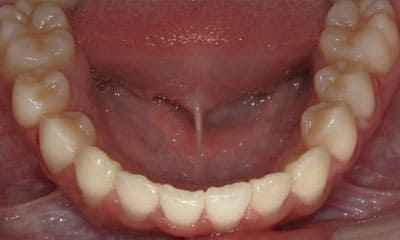

● 歯根が折れ保存不可の歯を抜歯して、そのスペースに八重歯を並べた症例

藤沢デンタルオフィスの虫歯や破折で抜歯後の部分矯正